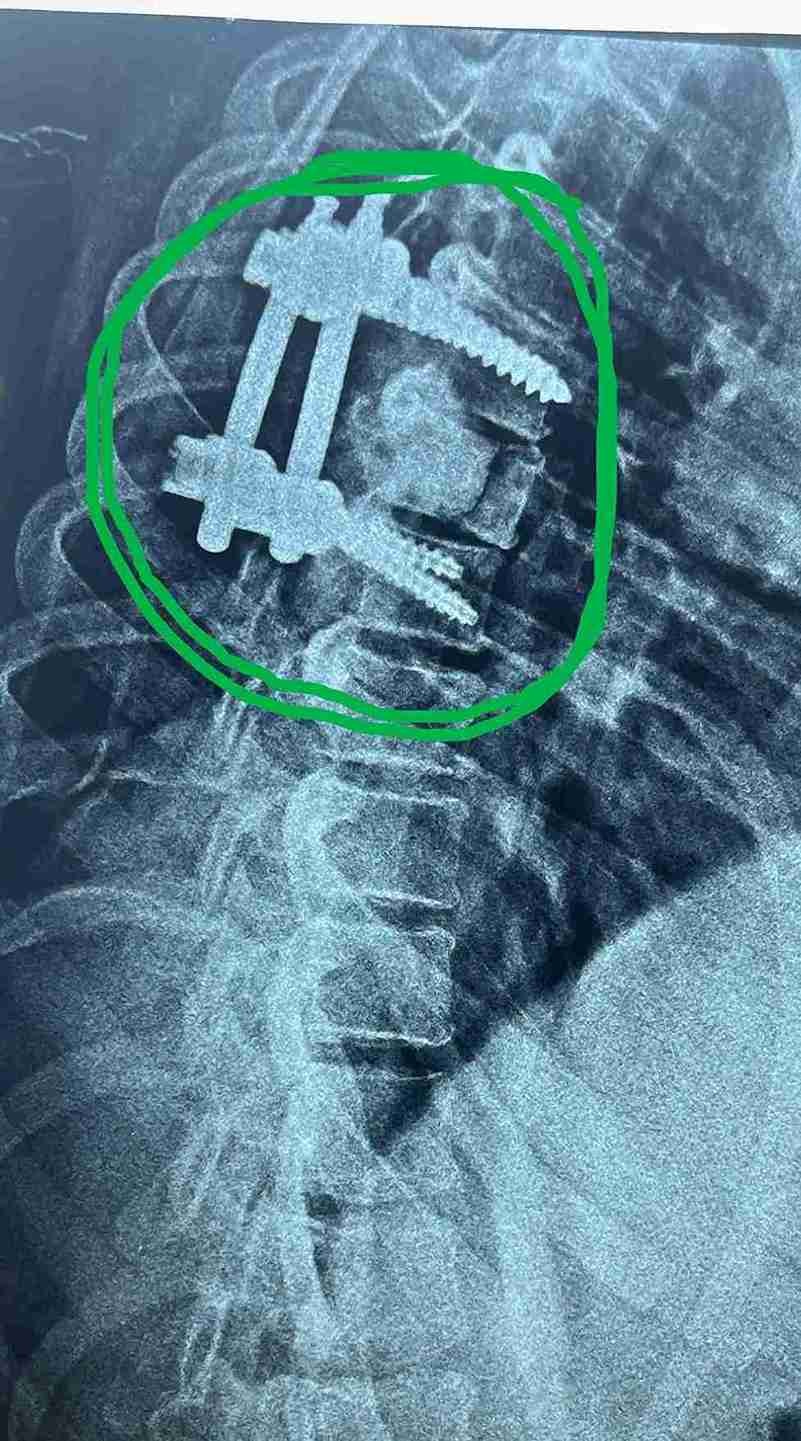

مريضة عمرها 43 عام تعاني من ضعف متزايد بالطرفين السفليين.

43-year-old female patient suffers from increasing weakness in the lower extremities

A 43-year-old woman suffering from progressive weakness in both lower limbs was diagnosed and treated. This condition affects walking ability and mobility, requiring thorough neurological evaluation to determine the underlying cause and develop an appropriate treatment plan.

Goal of Treatment

• Identifying exact cause of neurological weakness

• Developing comprehensive treatment plan